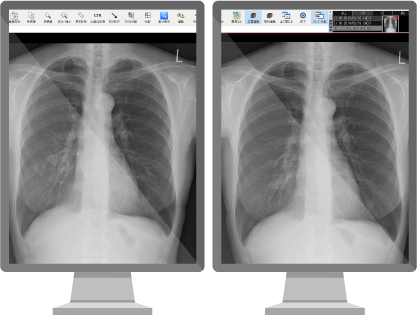

とにかく簡単・スムーズに読影したい!

- 問診、既往歴、前回結果をビューア上で確認可能

- ワンクリックで[異常なし登録]+[次の検査表示]

- あり得ない部位と所見の組み合わせは登録時に制御、手戻りを防ぐ

- 同一部位で複数マスタに対応し、読影方式も設定可能なレポート

視線移動やマウス移動を極力減らし、読影の負担を軽減。

他では真似できないスピーディな読影を可能にします!